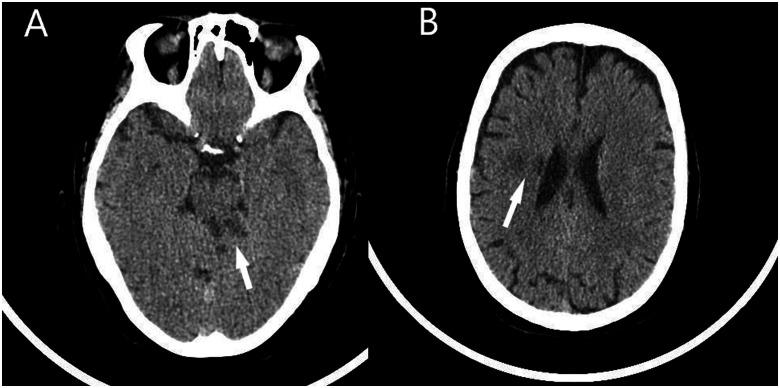

We present the case of a 66-year-old female with a history of AF and mechanical aortic and mitral valve replacement, which was admitted to the hospital complaining of dizziness and unsteady gait. A computerized tomography scan of the brain confirmed the diagnosis of embolic stroke. Two years later, the patient complained of sudden onset of chest pain, accompanied by electrocardiographic abnormalities and elevated high-sensitivity troponin T. Emergency cardiac catheterization revealed embolic myocardial infarction with distal occlusion of the obtuse marginal artery. Again, 2 years later, the patient suffered a new cerebral embolic event. Given the adequate anticoagulation therapy throughout almost the entire clinical course, percutaneous left atrial appendage closure was proposed as an adjunct to vitamin K antagonist treatment. Notably, intraprocedural transoesophageal echocardiography revealed the presence of a previously undetected left atrial appendage thrombus, thus an embolic protection device was used during the procedure, which was successfully carried out without complications.

我们报告一例66岁女性患者,有房颤病史,接受过机械主动脉瓣和二尖瓣置换术,因头晕和步态不稳入院。脑部计算机断层扫描确诊为栓塞性中风。两年后,患者主诉突发胸痛,伴有心电图异常及高敏肌钙蛋白T升高。急诊心脏导管检查显示为栓塞性心肌梗死,钝缘支动脉远端闭塞。又过了2年,患者发生了一次新的脑栓塞事件。鉴于几乎在整个临床过程中都进行了充分的抗凝治疗,建议采用经皮左心耳封堵术作为维生素K拮抗剂治疗的辅助手段。值得注意的是,术中经食管超声心动图显示存在一个先前未被发现的左心耳血栓,因此在手术过程中使用了栓塞保护装置,手术成功实施,未出现并发症。